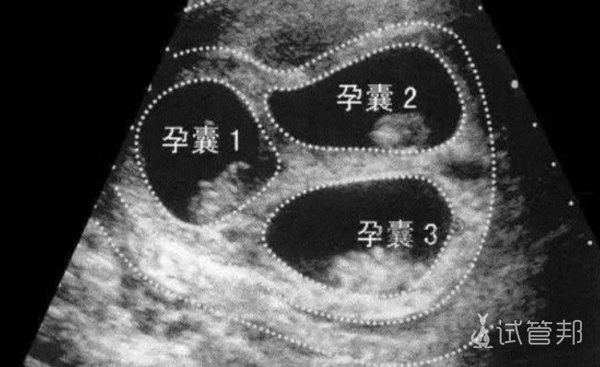

2024-10-23庆幸没有选择减胎,三胞胎宝宝都很健康

回想起去年这个时候,我还在为是否要减胎而纠结不已。但现在看看,幸好当初没有选择减胎,否则我就不会拥有现在这三个可爱的小宝贝啦!嘻嘻嘻~